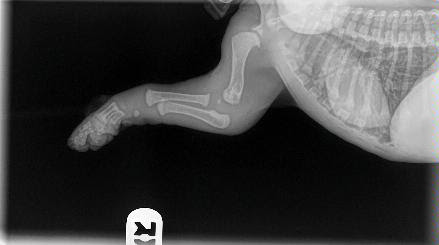

When you get your puppy, please keep these images in mind.

As you can see their bones are not even touching yet. Puppies are so cute when they jump around with their floppy little paws and wobbly legs because their joints are made up of tendons, muscle, and ligaments with skin covering. There is no socket yet and nothing fits tightly.

A bit of back-story: This is a baby puppy who had a knock to his elbow and wasn’t using it properly, so he was taken to the vet. There is nothing wrong in these x-rays, thankfully it is a soft tissue injury and he is expected to be fine.